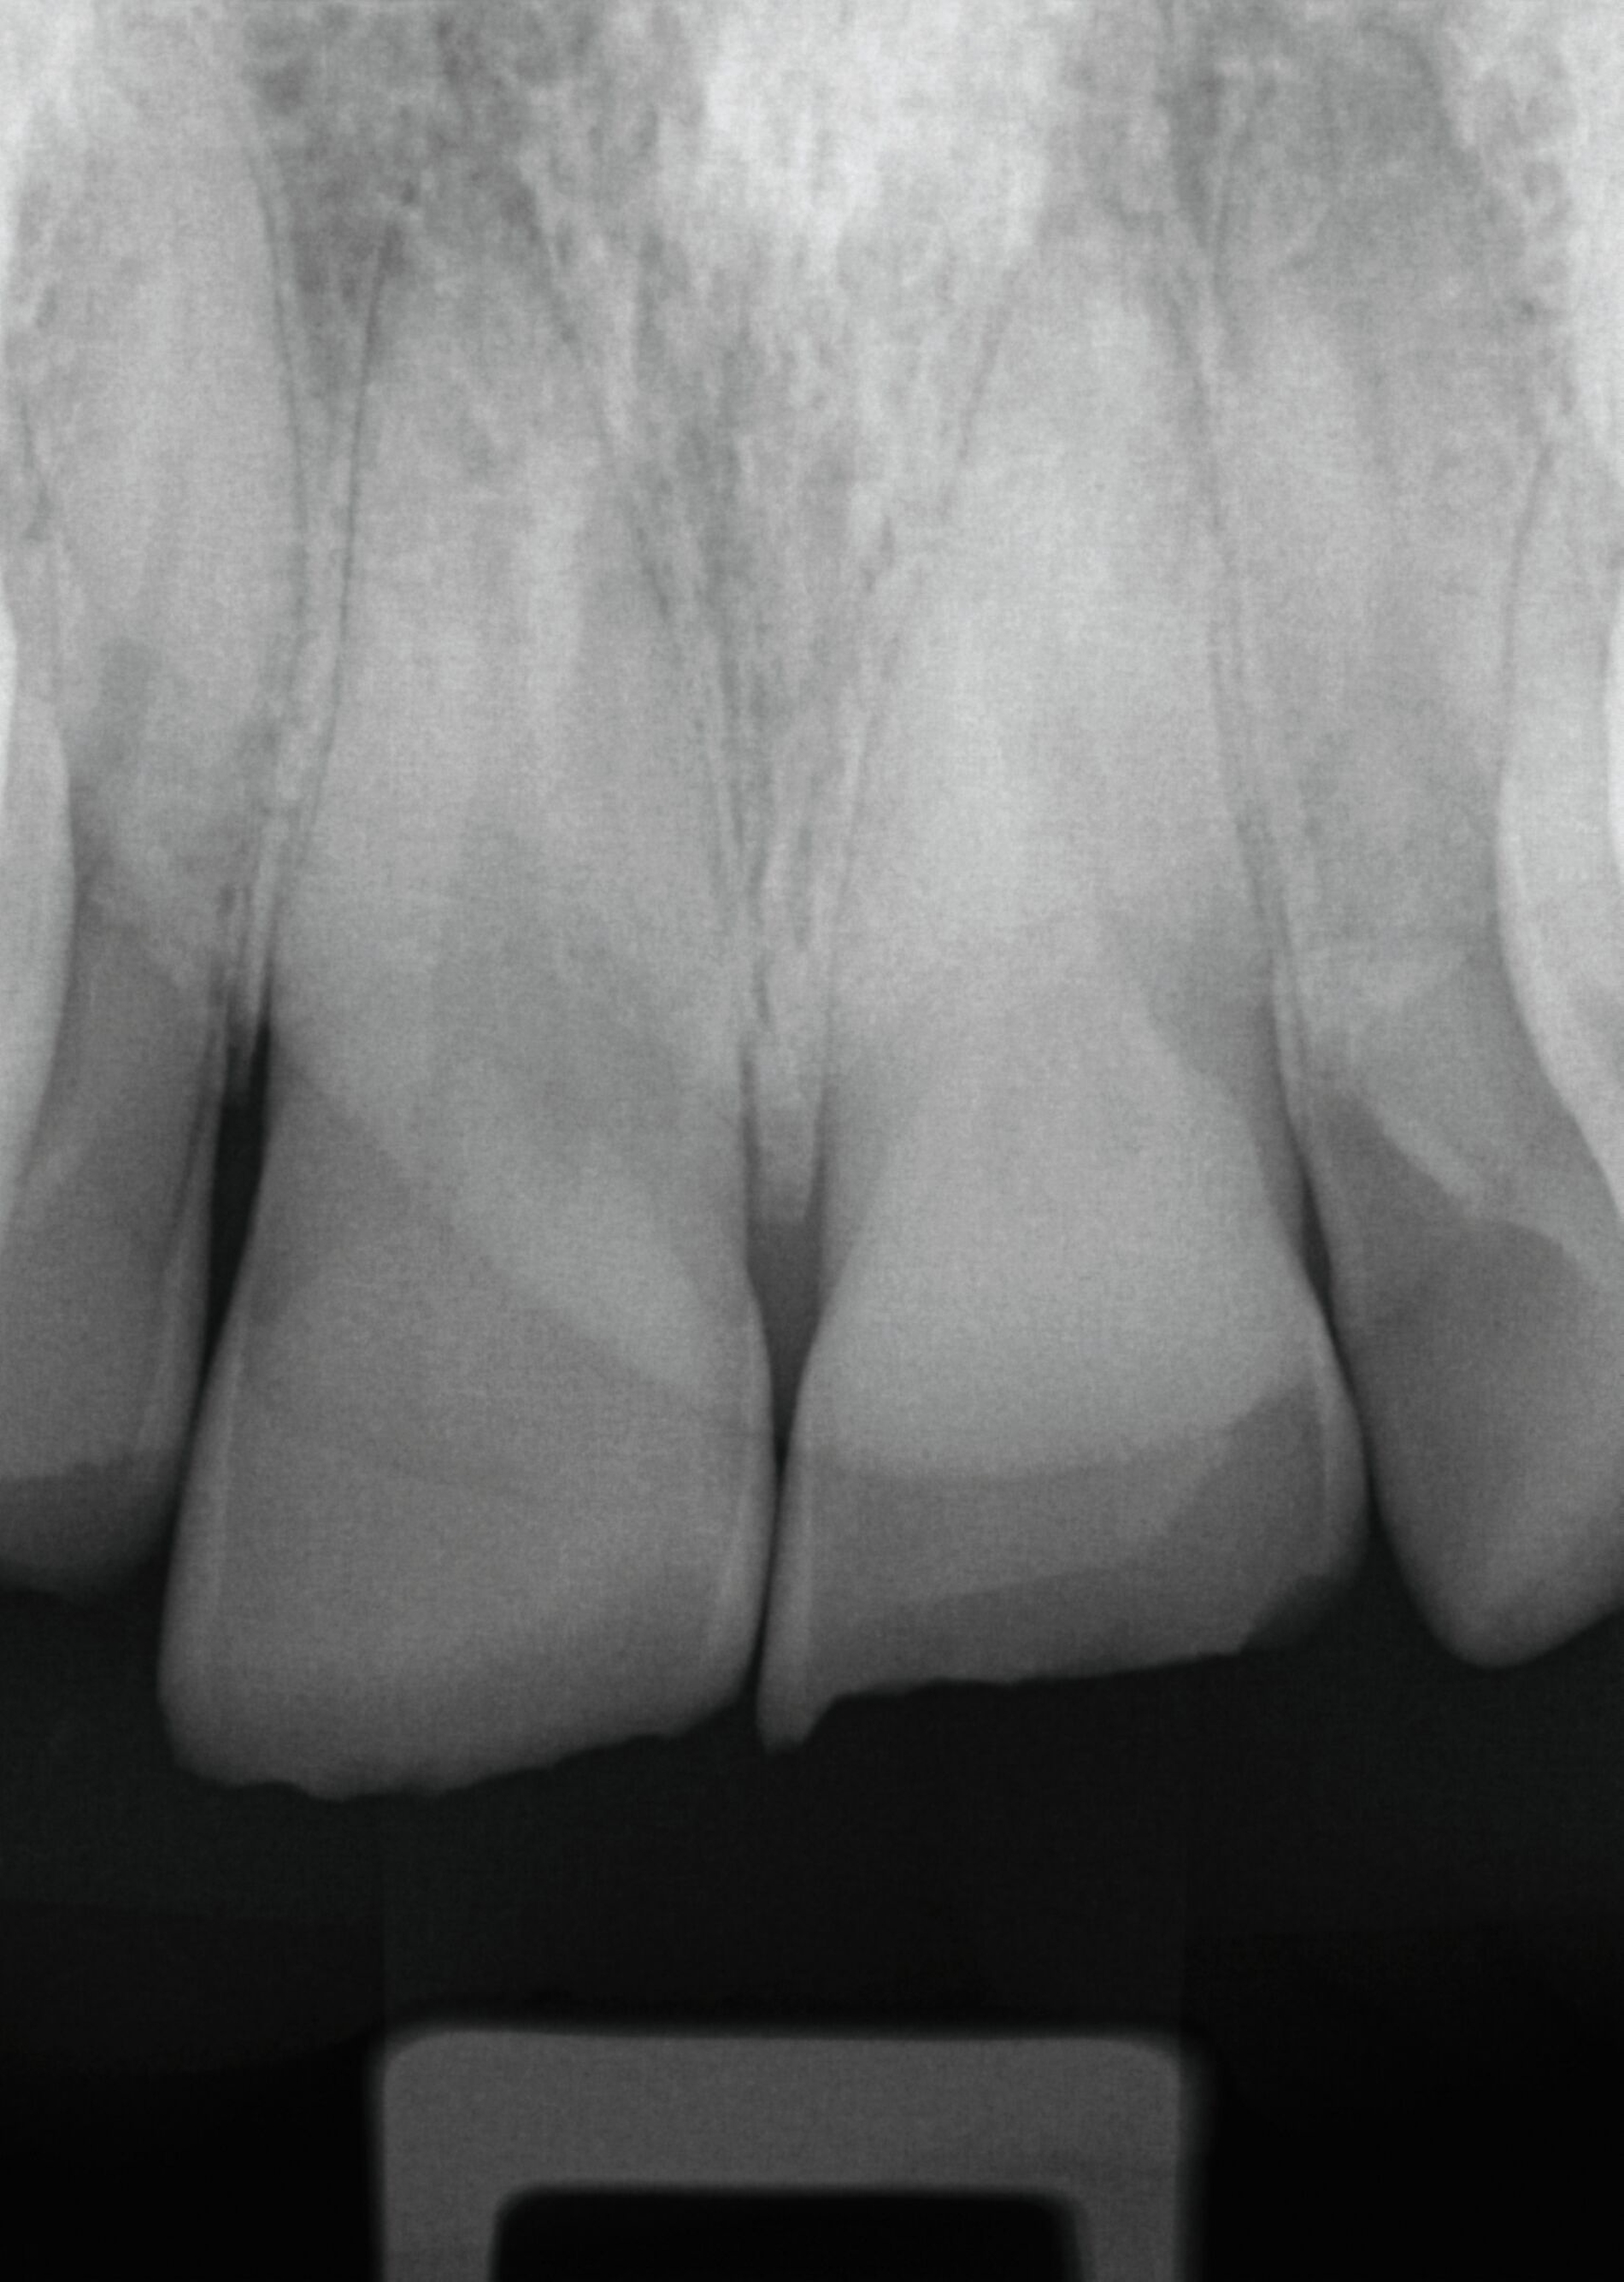

Um potenzielle Komplikationen nach einem Zahntrauma möglichst frühzeitig zu erkennen, werden entsprechend den Empfehlungen der S2k-Leitlinie regelmäßige röntgenologische und klinische Nachkontrollen durchgeführt. Exemplarisch sind hier die Röntgenbilder nach drei Monaten und 1,5 Jahren dargestellt (Abbildung 3).